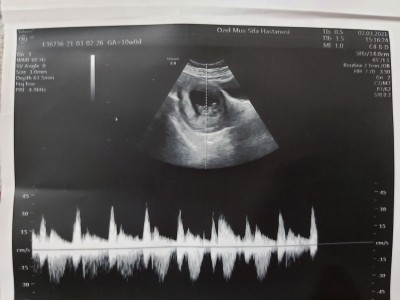

Ultrason fotoğrafında fhr yazan kalp atis hiziydi ama benimkinde yazmıyo. Acaba baska sekilde mi yaziyo ne dersiniz?

Gebelik haftası 10

Canım maşallah sübhanallah :) aşağıda çizgiler var ya o kalp atışı oluyor her alette yazmaya bilir fhr rabbim sağlıkla kucağına almayı nasip etsin :)